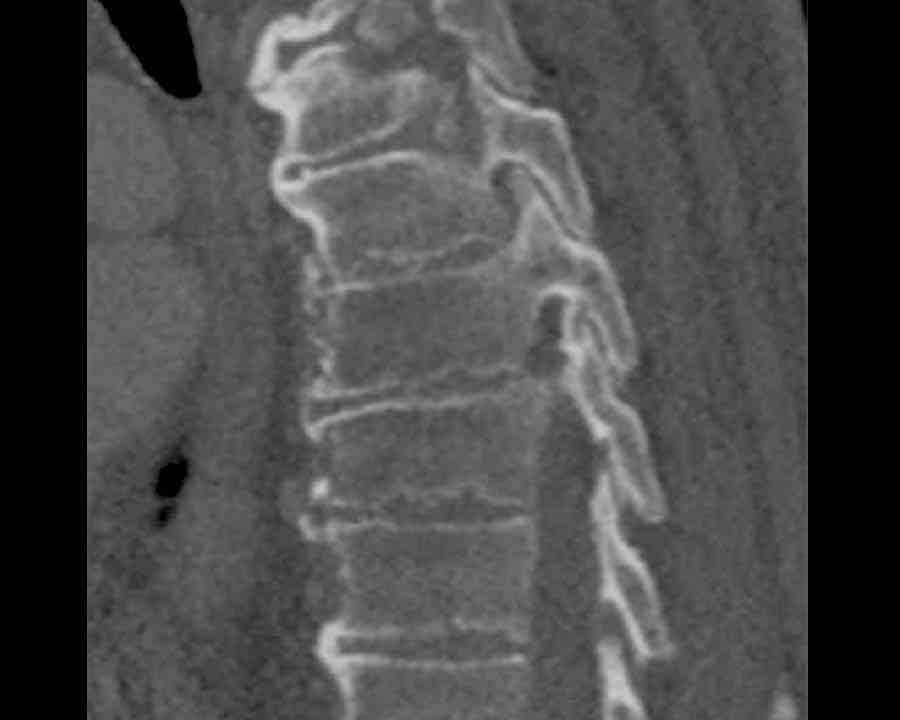

Scroll through images.

What are the findings?

Findings

- C injury? No.

- Signs of a rigid spine?

Yes, so be aware of potentially very subtle B3 injury. - A subtle fracture on the anterior vertebral body is seen (arrows).

Conclusion

Injury type B3.